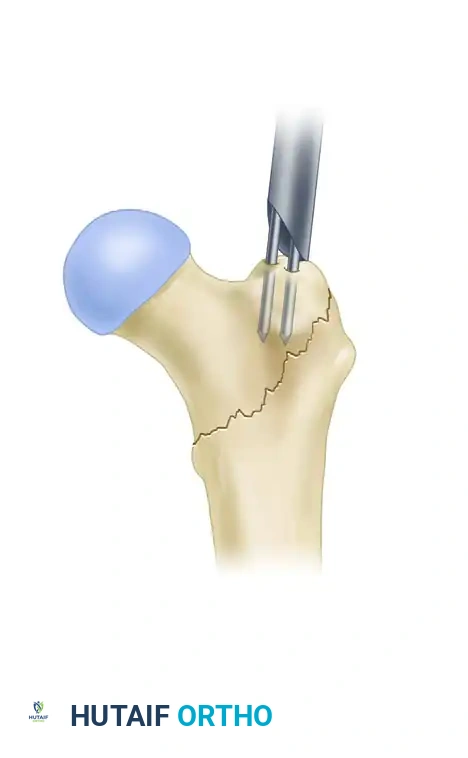

Image

Utilization of a dedicated reduction tool to manipulate the proximal fragment and align the medullary canal.